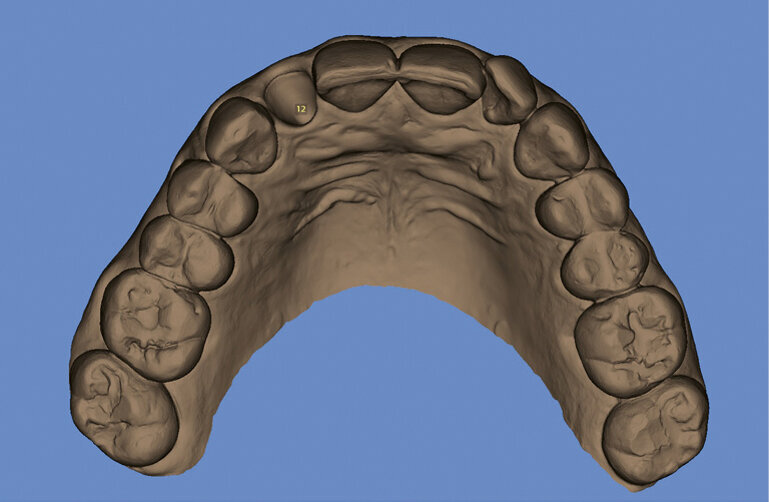

Fig. 3. Surface scan of the preoperative situation

The process begins by obtaining a high-quality portrait photograph, a DVT and an STL file (Figs 1 to 3). In the case presented here, tooth 12 can no longer be preserved and needs to be replaced with an implant prosthetic restoration. Designing the prosthetic restoration forms the first stage of the implant planning sequence. In the present case, the shape of the existing tooth should be maintained. If an analogue workflow is followed, the premise for the implant is the extraction of the tooth. This scenario also forms the first step in the digital procedure described here - however, the tooth is “only” extracted virtually. We can extract the tooth digitally to design e.g. the future alveolar cavity (emergence profile) and generate an optimized emergence profile. An alveolar model is required for:

The implant crown is designed (virtual wax-up). In the present case, the tooth being replaced serves as the template. The crown reflects the position and proportions of the original tooth. A copy of the scan file is again used as working file on which the virtual tooth extraction is performed. This allows us to go back to the original data and compare it with the working file. We define the ideal implant placement position and design the peri-implant soft tissue contours on the screen to provide an adequate emergence profile (Fig. 4). We then prepare a drill template for safe transfer of the implant position to the oral cavity. Even though most dentists are familiar with this procedure, we will briefly address the fundamentals: Basically, three data sets are required for preparing a drill template: